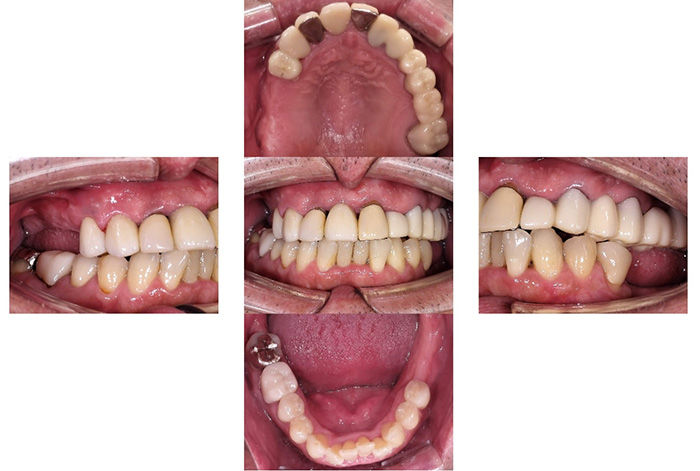

Before

After

インビザラインによる全体矯正後に補綴治療を行い、咬合と審美性を総合的に改善した症例です。

まずマウスピース型矯正装置(インビザライン)により歯列および咬合関係を整え、その後、必要部位にジルコニア補綴を行いました。

矯正のみ・補綴のみではなく、両治療を組み合わせることで機能性と審美性の両立を目指した包括的治療です。

奥歯の噛み合わせと前歯の歯並びを同時に改善した症例(インビザライン+ジルコニア)

【治療前の状態】

患者様は、奥歯でしっかり噛めないことと、前歯の歯並びの乱れを気にされ来院されました。診査の結果、前歯部の叢生(歯並びの乱れ)と、臼歯部の離開咬合(奥歯がしっかり噛み合っていない状態)が認められました。また、臼歯部には古い金属修復物が装着されており、機能面だけでなく審美面においても改善が必要な状態でした。

【治療後】

前歯の歯並びが整い、見た目の改善が認められました。また、奥歯でしっかり噛める状態となり、咬合機能の回復が得られています。

【治療のポイント】

本症例では、歯並びの改善だけでなく、噛み合わせの回復と審美性の向上を同時に行っています。当院は一般歯科と矯正治療の両方に対応しているため、矯正治療後に別の医療機関で補綴治療を行う必要がなく、一貫した治療計画のもとで治療を完結することが可能です。また、奥歯の噛み合わせを矯正治療のみで改善する場合、治療期間が長くなることがありますが、本症例では補綴治療(アンレー)を併用することで、比較的短期間で咬合の改善を行いました。さらに、古い金属修復物をジルコニアに置き換えることで、見た目の改善と機能性の両立を図っています。